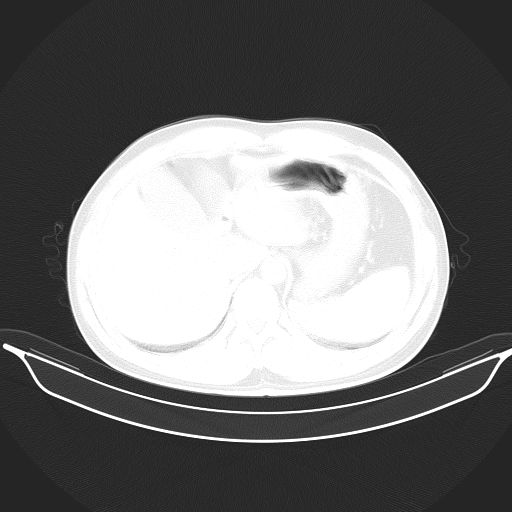

标题: CT25490:男,40岁,体检发现;无其它不适。 [打印本页]

标题: CT25490:男,40岁,体检发现;无其它不适。

2、轻度脂肪肝。

转移性肺肿瘤不排除,建议结合相关检查考虑

1、均为转移,原发灶不在肺内。2、肺癌肺转移。